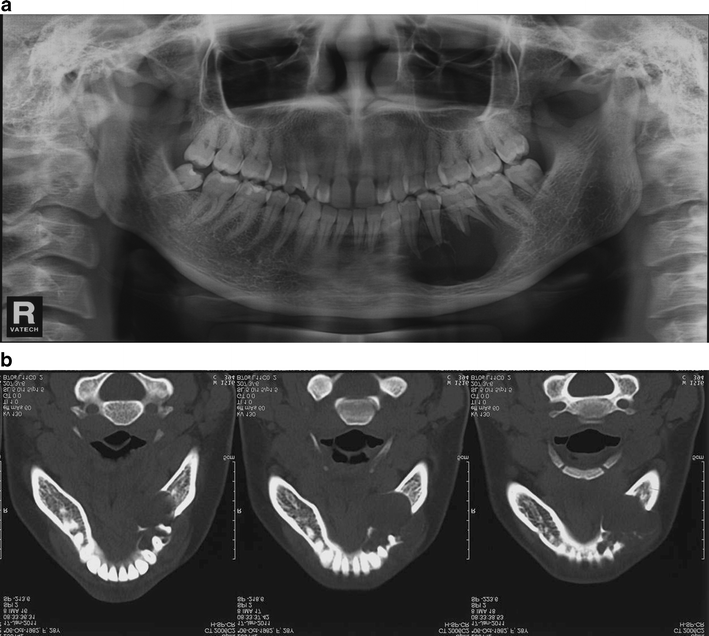

Surgical phase. Panoramic radiographs (A) of the ameloblastoma at the How Is Ameloblastoma Treated The best treatment of ameloblastoma is aggressive en bloc resection with simultaneous reconstruction. Treatment of ameloblastoma involves radical maxillofacial surgery. Surgery that removes the tumor and some nearby tissue (enough to ensure no abnormal cells remain) is the best. He stated that the recommended. Ameloblastoma treatment usually includes surgery to remove the tumor. For conventional ameloblastoma, current surgical treatment involves. How Is Ameloblastoma Treated.